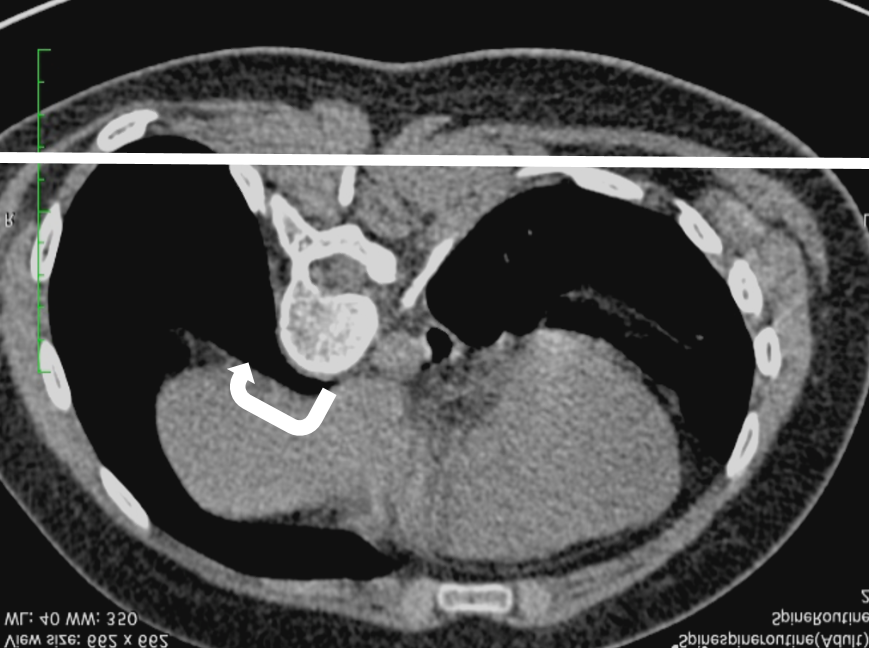

КТ позвоночника у пациента с идиопатическим правосторонним сколиозом.  Позвонки повернуты по часовой стрелке, скручивают грудную клетку и приподнимают ребра справа